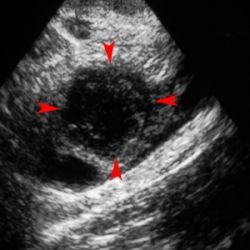

С наступлением беременности в женском организме начинают происходить разнообразные биохимические процессы, необходимые как для сохранения, так и для развития плода. Сегодня мы предлагаем узнать о механизме, выполняющем одну из главных ролей в этом процессе, - о желтом теле.